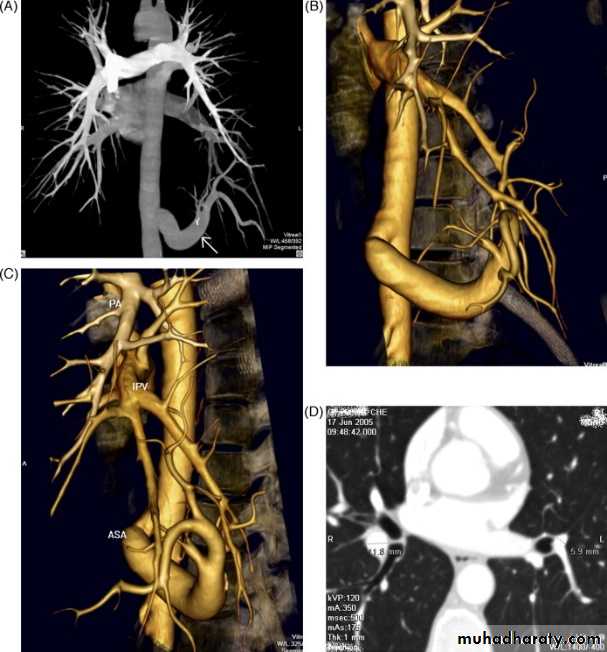

Multidetector CT

• Helical (spiral) CT scanners became available in the early 1990s.

• Multidetector row CT (MDCT)/ multislice CT (MSCT), was developed in the mid to late 1990s.

• In conventional scanners, the tube and detectors rotate as the patient passes through on the scanning table.

• In helical CT a circular gantry holding the X-ray tube on one side and detectors on the other rotates continuously as the patient passes through.

• The difference with MDCT is that instead of a single row of detectors multiple detector rows are used.

• The original MDCT scanners used two or four rows of detectors, followed by 16 and 64 detector row scanners. At the time of writing, 256 and 320 row scanners are becoming widely available.

• Multidetector row CT allows the acquisition of overlapping fine sections of data, which in turn allows the reconstruction of highly accurate and detailed 3D images as well as sections in any desired plane.

The major advantages of MDCT over conventional CT scanning are:

• Increased speed of examination• Rapid examination at optimal levels of intravenous contrast concentration

• Continuous volumetric nature of data allows accurate high-quality 3D and multiplanar reconstruction.

MDCT applications including:

• CT angiography: coronary, cerebral, carotid, pulmonary, renal, visceral, peripheral

• Cardiac CT, including CT coronary angiography and coronary artery calcium scoring